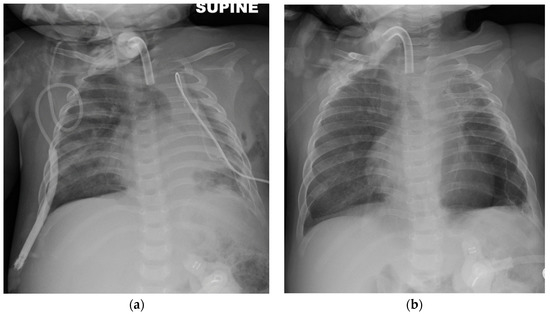

2. Case Presentation